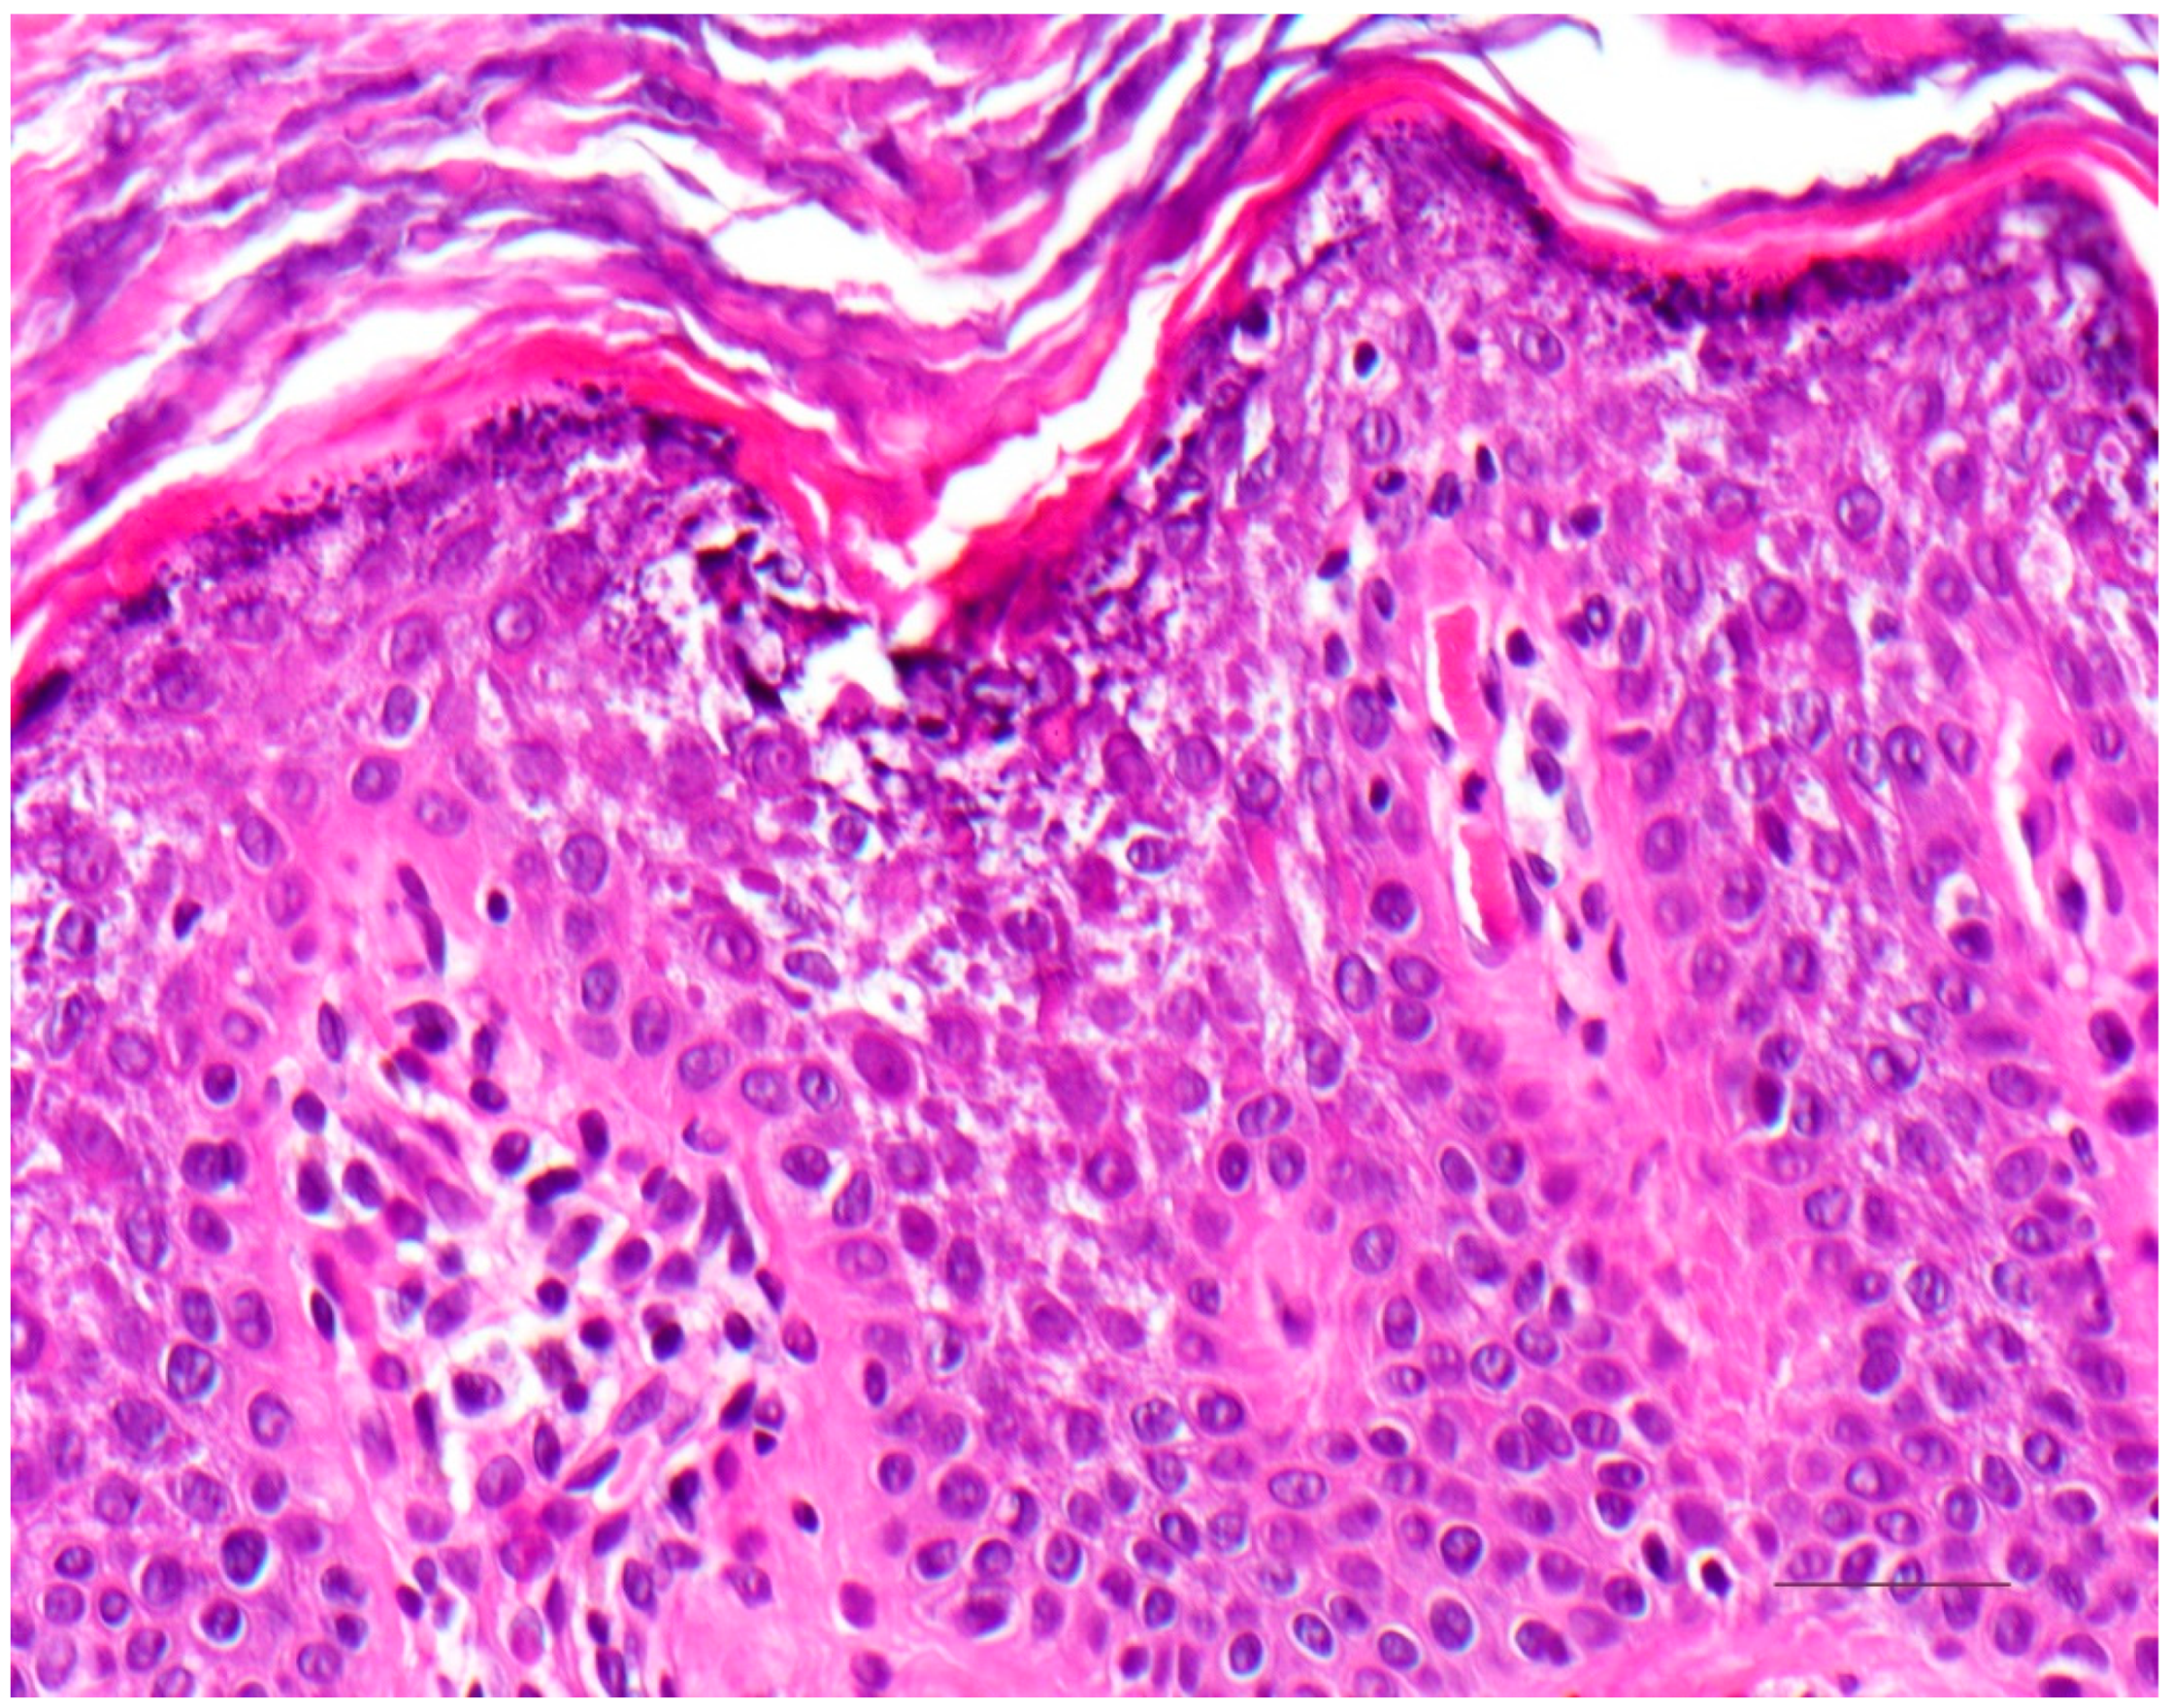

5. Keratinopathic Ichthyosis

5.1. Histology